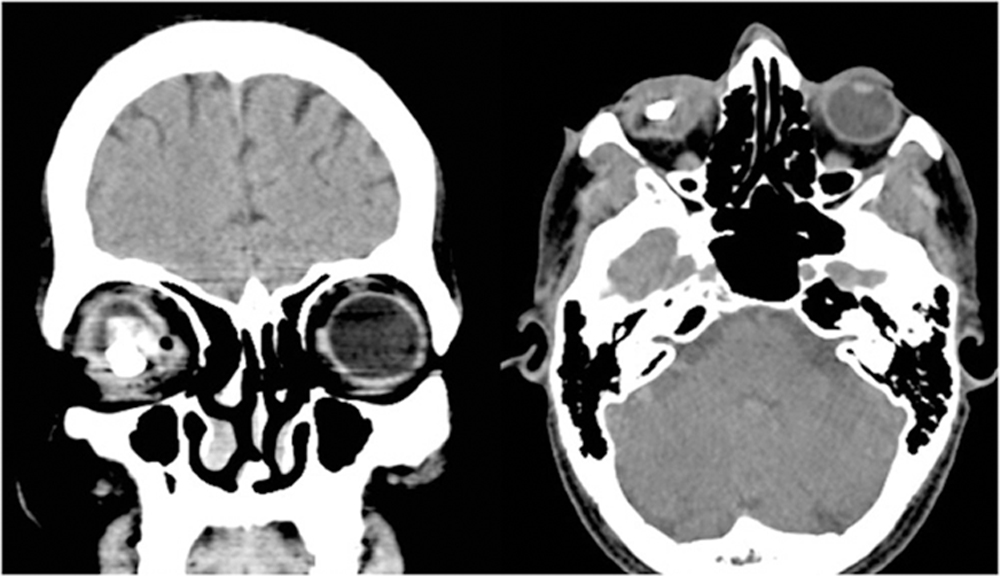

A 42 year old male presented with history of penetrating trauma in right eye while standing beside a stone cutter. At presentation visual acuity was no light perception. Clinical examination revealed scleral tear on nasal side. Posterior extent could not be ascertained. Cornea was clear. Hyphema precluded view of fundus. Eyeball appeared collapsed. CT scan examination showed a large radio-opaque IOFB with collapsed eyeball (Fig 2). Surgery was planned for wound exploration and suturing and removal of IOFB to prevent traumatic endophthalmitis. Intraoperatively scleral wound was explored to the posterior extent after disinsertion of medial rectus muscle and sutured with 6-0 vicryl suture with hand over hand technique. Lensectomy was performed through limbus. Standard 3 port pars planavitrectomy performed with 23G TSV system. A large stone IOFB along with total RD and vitreous hemorrhage were noted. Posterior vitreous detachment was absent. IOFB was released of all vitreous attachments and IOFB was lifted to papillary plane using the Claw (Fig 3). Superior 180 degrees limbal section was made and IOFB removed with superior rectus holding forceps by handshake technique. It measured 10mm X 5mmX 4mm (Fig 4).

- Fig2: CT scan images showing deformed eyeball with large IOFB

Figure 2: